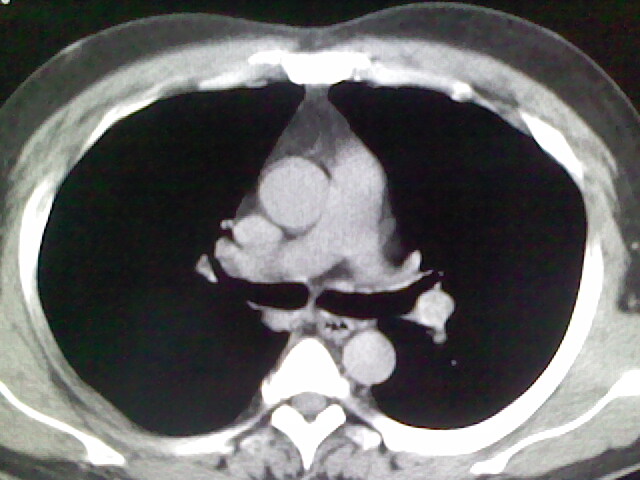

标题: CT17932:临床怀疑肺栓塞

男,34岁,自觉右侧胸痹,胸闷3天余

右侧肺动脉似见密度稍低影,请在机器的薄层上再看看有没有充盈缺损。